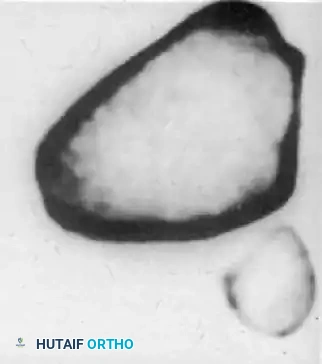

لفهم كيف يحدث خلع المفصل الوركي الرضحي، يجب أولاً أن نتعرف على التصميم التشريحي المذهل لهذا المفصل. يُصنف مفصل الورك على أنه مفصل زلالي من نوع الكرة والتجويف.

تتكون الكرة من رأس عظمة الفخذ الدائري، بينما يتمثل التجويف في تجويف عميق في عظمة الحوض يُسمى الحق. هذا التصميم العميق يوفر تغطية واسعة لرأس عظمة الفخذ، مما يمنحه استقراراً عظمياً فائقاً.

لا يقتصر الاستقرار على العظام فقط، بل يُعزز بوجود حلقة غضروفية ليفية تُعرف باسم الشفا الحقي، والتي تعمل كختم مطاطي يزيد من عمق التجويف. بالإضافة إلى ذلك، يُحاط المفصل بمجموعة من الأربطة القوية جداً، وعلى رأسها الرباط الحرقفي الفخذي، والذي يُعد أقوى رباط في جسم الإنسان على الإطلاق، حيث يمنع خروج عظمة الفخذ من مكانها بسهولة. بسبب هذا الاستقرار الداخلي العميق، لا يمكن أن يحدث خلع في مفصل الورك السليم إلا نتيجة صدمة عالية الطاقة.